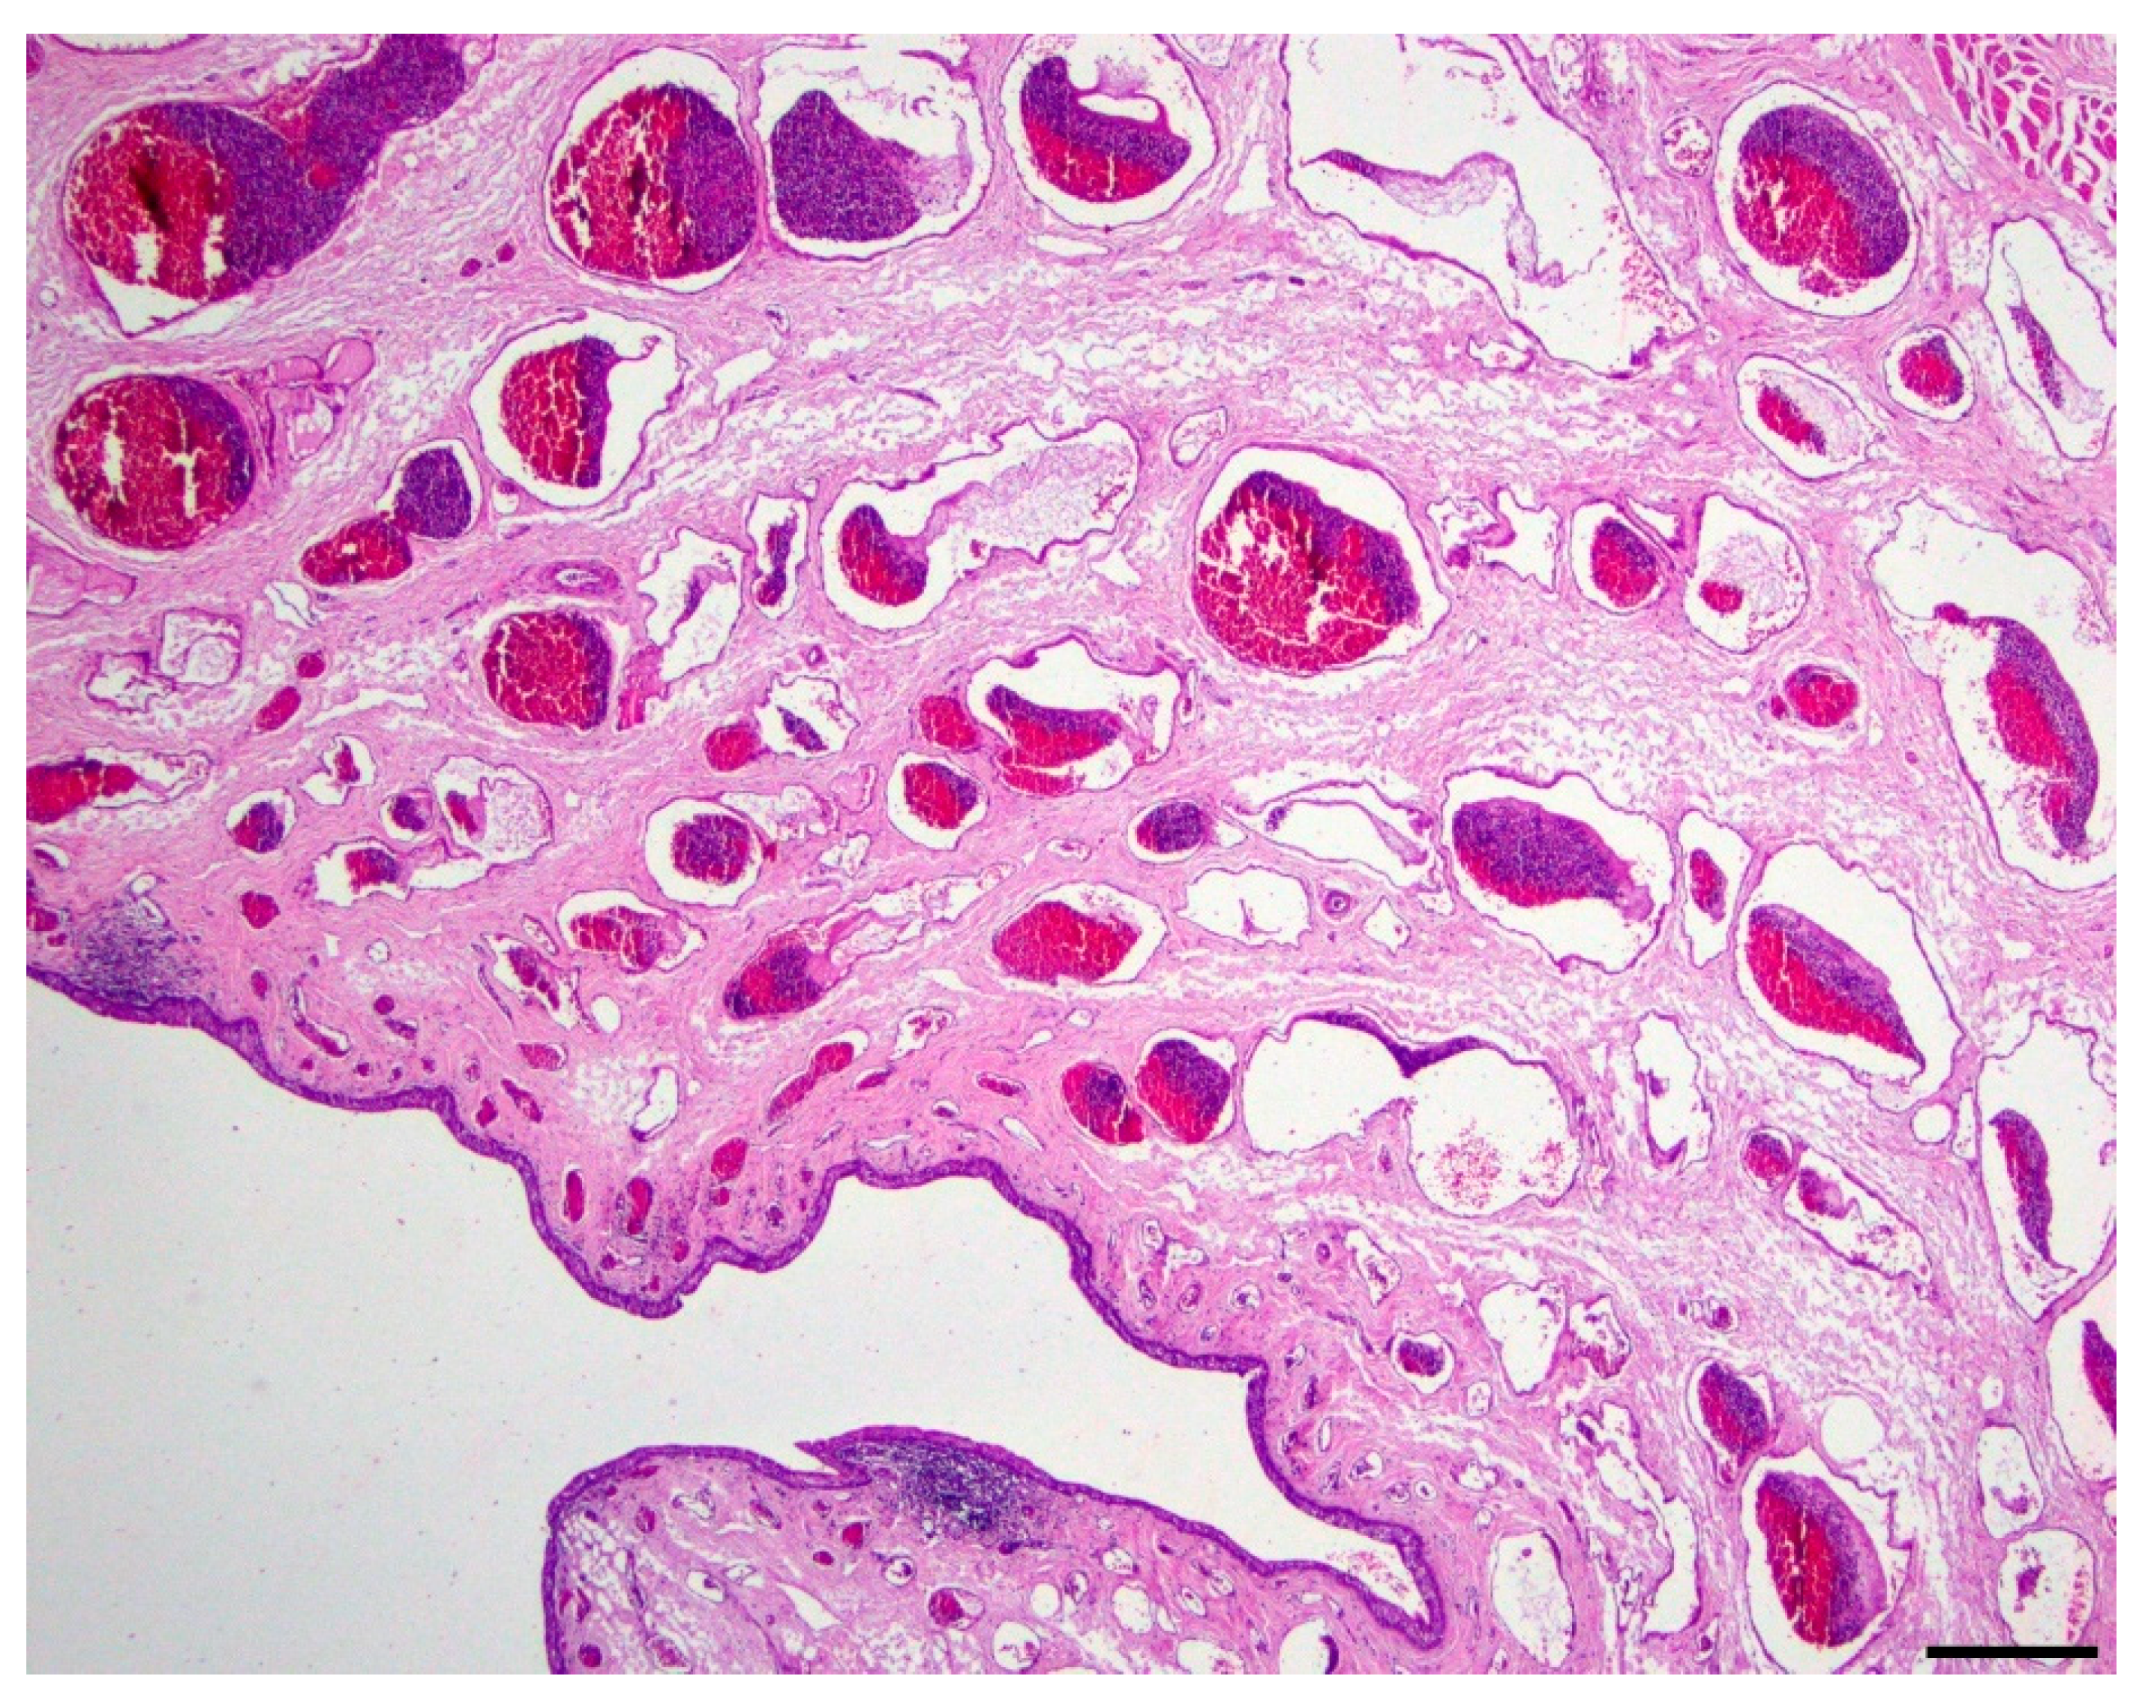

Microscopic evaluation of the mass revealed an unencapsulated, moderately cellular, well-demarcated expansile mass (Figure 1). The mass was centered on a lumen lined primarily by urothelium that multifocally transitioned to non-keratinizing, stratified-squamous epithelium (Figure 2). In portions of the mass lined by stratified squamous epithelium, the supporting stroma contained low numbers of hair follicles and associated sebaceous sweat glands with scattered apocrine glands (Figure 3). The lumen was surrounded by a dense collagenous stroma with few skeletal muscle bundles containing numerous, variably sized, dilated vascular channels with luminal erythrocytes (Figure 4). The vascular channels occasionally anastomosed and were lined by a single layer of endothelium. The sub-urothelial collagenous stroma was multifocally infiltrated and expanded by aggregates of lymphocytes and fewer plasma cells forming discrete aggregates (Figure 3).

Figure 1. Cross section of entire mass (20x; hematoxylin and eosin). The mass is composed of a moderately dense fibrovascular stroma containing numerous blood-filled channels surrounding a lumen lined primarily by urothelium with multifocal aggregates of well-differentiated hair follicles and associated adnexal structures; bar = 2 mm.